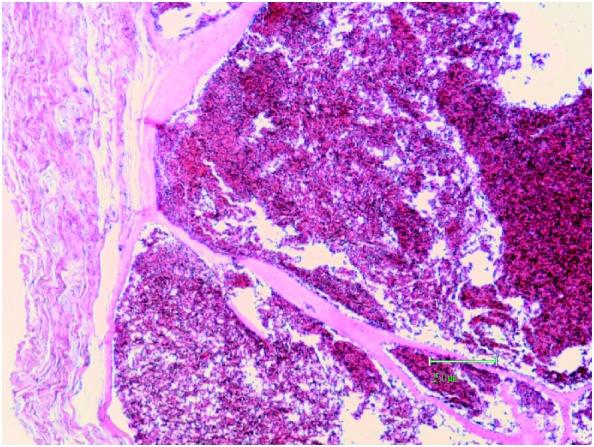

Surface-based bone hemangiomas are uncommon, mostly occurring in long bones of the lower extremities. Radiographic surface-based bone hemangioma images may present various features that provide a diagnostic challenge. We report a case of surface-based hemangioma of the radius that posed radiological diagnostic difficulties. The tumor size was small and the cortical reaction was subtle. MRI findings were nonspecific and angiography was useful in the assessment of painful but less obvious surface-based bone hemangioma. The patient's pain improved following surgery and no tumor recurrence was observed at 3 years after surgery.

骨表面血管瘤并不常见,多发生于下肢长骨。基于影像学的骨表面血管瘤图像可能呈现出各种特征,给诊断带来挑战。我们报告一例桡骨骨表面血管瘤病例,该病例在放射学诊断上存在困难。肿瘤体积较小,皮质反应不明显。磁共振成像(MRI)表现不具有特异性,血管造影术有助于评估疼痛但表现不明显的骨表面血管瘤。患者术后疼痛改善,术后3年未观察到肿瘤复发。